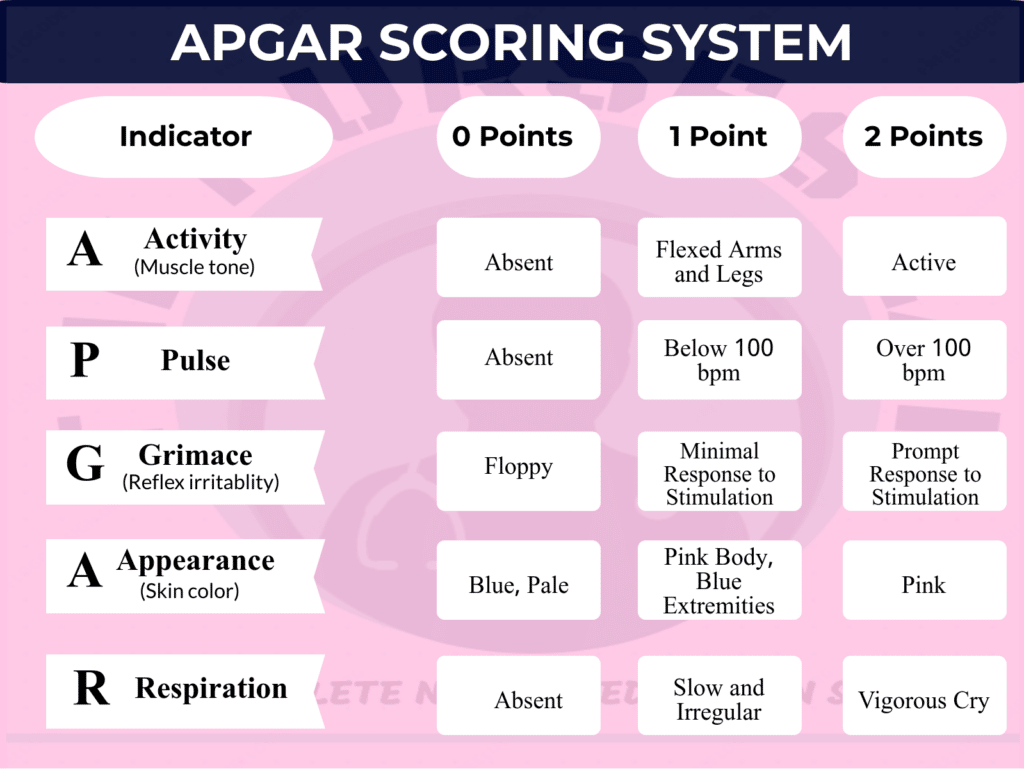

The moments after birth are busy ones! Whether at home or the hospital, making sure mom and baby are safe is the top priority. Apgar scores are provided one and five minutes after birth. Ocassionally, a third score will be provided after 10 minutes. The 1-minute score evaluates a newborn's tolerance to the birth process; the 5-minute score evaluates a newborn's adaptability to its surroundings, and its capacity to recuperate after birth. For most, the 1-minute score will be slightly (or sometimes significantly) lower than the 5-minute score. Each element of the test has a scoring scale of 0 – 2. Its purpose is to determine if there is a need for additional care within the first minutes after birth.

Most babies have an Apgar score between 7 – 10 points. Getting a full 10 points is extremely rare because most babies have slightly blue extremities immediately after birth. A “perfectly pink” baby is the exception, not the norm. Although some babies have lower scores (between 5 -7), they tend to bounce back within the time they are in the hospital.

When creating the score, your baby's healthcare provider will examine the following aspects:

Appearance: : A baby’s skin color after birth says a lot about their circulatory system. The goal is to see properly perfused skin, indicating adequate oxygen levels and blood flow throughout the body.

Pulse: : A strong pulse indicates a healthy heart and its capacity to properly pump blood.

Grimace: : This score is achieved by examining a baby’s reflexive behaviour. There are different ways to do this. The most common things include: coughing, pulling away, crying when stimulated and facial expressions.

Activity ( muscle tone) : ): A moving baby is a good thing and it’s ideally what everyone wants to see. Some babies have more movement than others at birth and that’s okay. Again, it may take the baby a few minutes to become fully active.

Respiration: A vigorous cry will score a baby 2 points in this category. However, not all babies come out making their presence known. If a baby is born by C-section, they are more likely to need a bit of stimulation before that first loud cry. Why? A C-section doesn't provide the same stimulation to the lungs as a vaginal birth. During a vaginal birth, the pressure created helps release fluid from a baby’s lungs. Additionally, the effects from some of the birth hormones help the liquid in a baby’s lungs dry up faster.